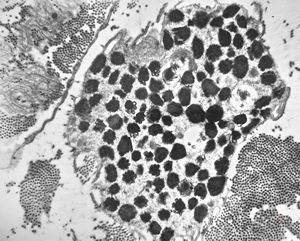

M,3y. | mast cell - n. suralis, Krabbe globoid leukodystrophy

F,23y. | mast cell - n. suralis, demyelinating neuropathy

M,3y. | mast cell - granules with scroll-like formations - n. suralis, Krabbe globoid leukodystrophy

M,3y. | mast cell - granules with scroll-like formations - n. suralis, Krabbe globoid leukodystrophy

F,23y. | mast cell - granules with scroll-like formations - n. suralis, demyelinating neuropathy

F,31y. | mast cell - granules with scroll-like formations - n. suralis, demyelinating neuropathy

M,12y. | mast cell - granules with scroll-like formations - skin, urticaria pigmentosa